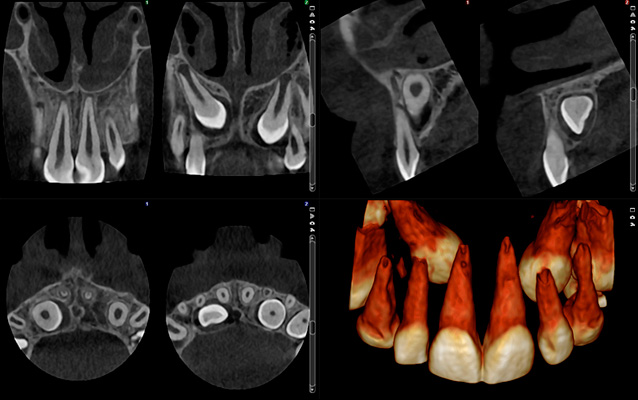

Immagini a ultra basso dosaggio – Caso ortodontico

Planmeca ProMax 3D - FOV Ø 85 x 50 mm. - Dimensioni voxel 400 µm - Dosaggio effettivo del paziente 7,9 µSv

Planmeca ProMax 3D - FOV Ø 85 x 50 mm. - Dimensioni voxel 400 µm - Dosaggio effettivo del paziente 4,0 µSv